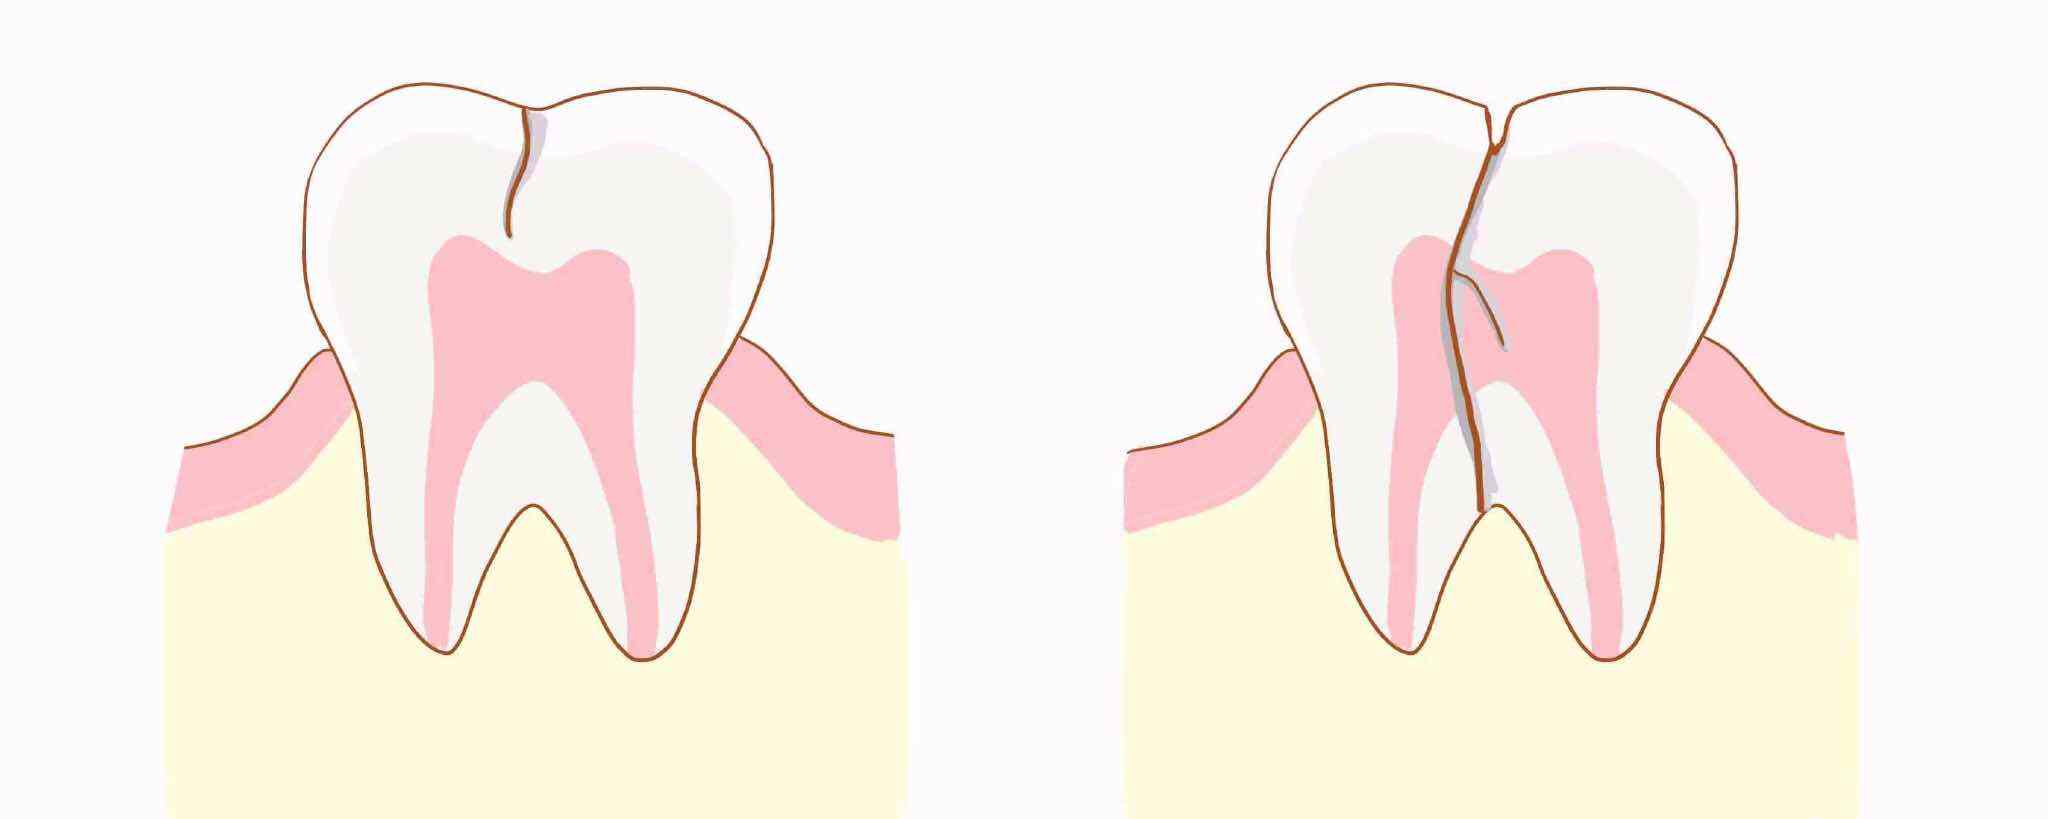

如果我们的牙齿受到外伤,或者是咬了硬的东西,或者发生疾病,都有可能会出现牙齿裂了的情况,那么,牙齿裂了怎么办?

假如牙齿虽然裂了,但是裂纹小,可以使用纳米材料填充,当然,树脂填充也可以,利用它们将牙齿裂纹填充好就可以了。

如果牙齿只是有浅表的裂纹,而且患者也没有什么不舒服,牙髓的活力无异常,可以调牙治疗,医生还有办法让患者的牙齿裂纹不再加深。